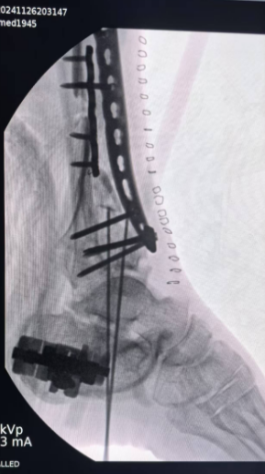

在手术过程中,王瑞国手术团队利用先进的影像学检查技术,精准定位每一处骨折线与碎骨片,为手术提供了详尽的蓝图。随后,团队创新性地采用双反牵引架进行牵引复位,为手术创造了良好的视野和操作空间。在专家的精湛技艺下,碎骨被逐一复位,关节面得到精心重建。最终,内固定钢板与外固定支架的联合应用,如同坚固的桥梁支架,确保了复位后的骨骼在愈合过程中的稳定性。